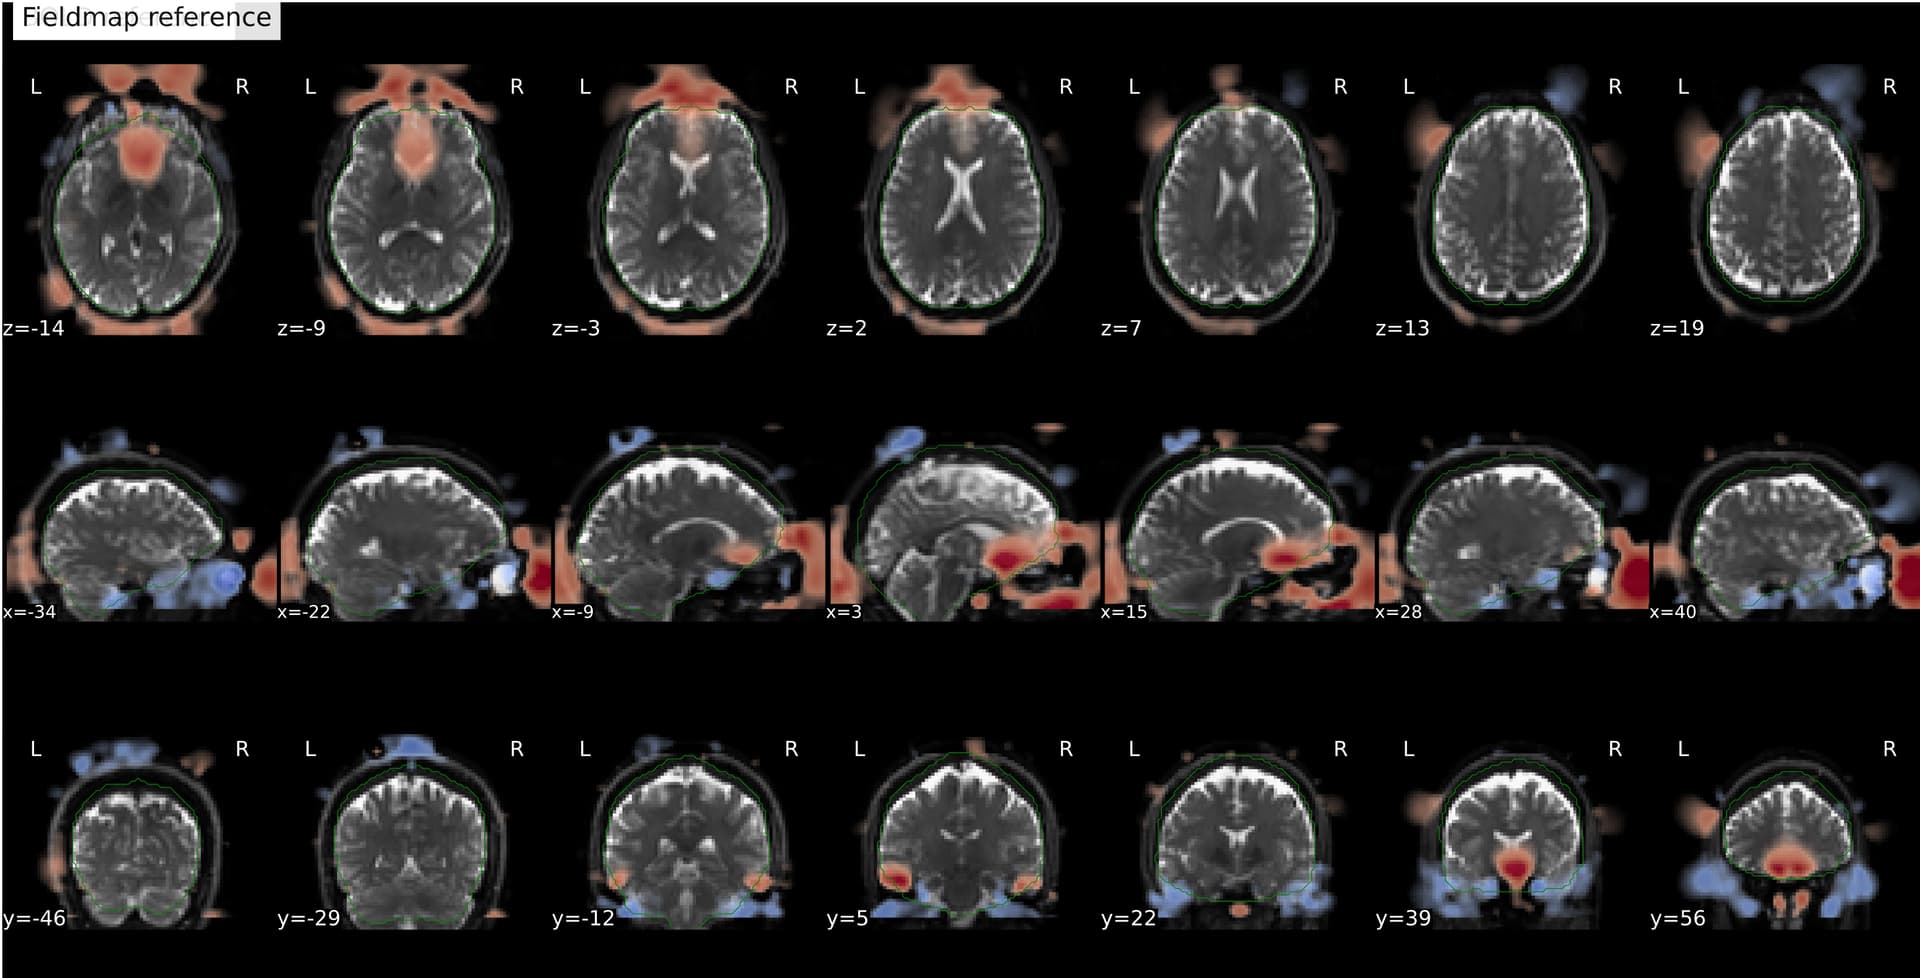

Another example:

I’m seeing an apparent misalignment in the fmapCoreg reportlet for a PEPOLAR (SE-EPI AP/PA) distortion-correction workflow

- The SDC before/after panel looks okay-ish, suggesting distortion correction itself is likely working somehow, but poor than for subjects where fmap-bold coreg works as expected.